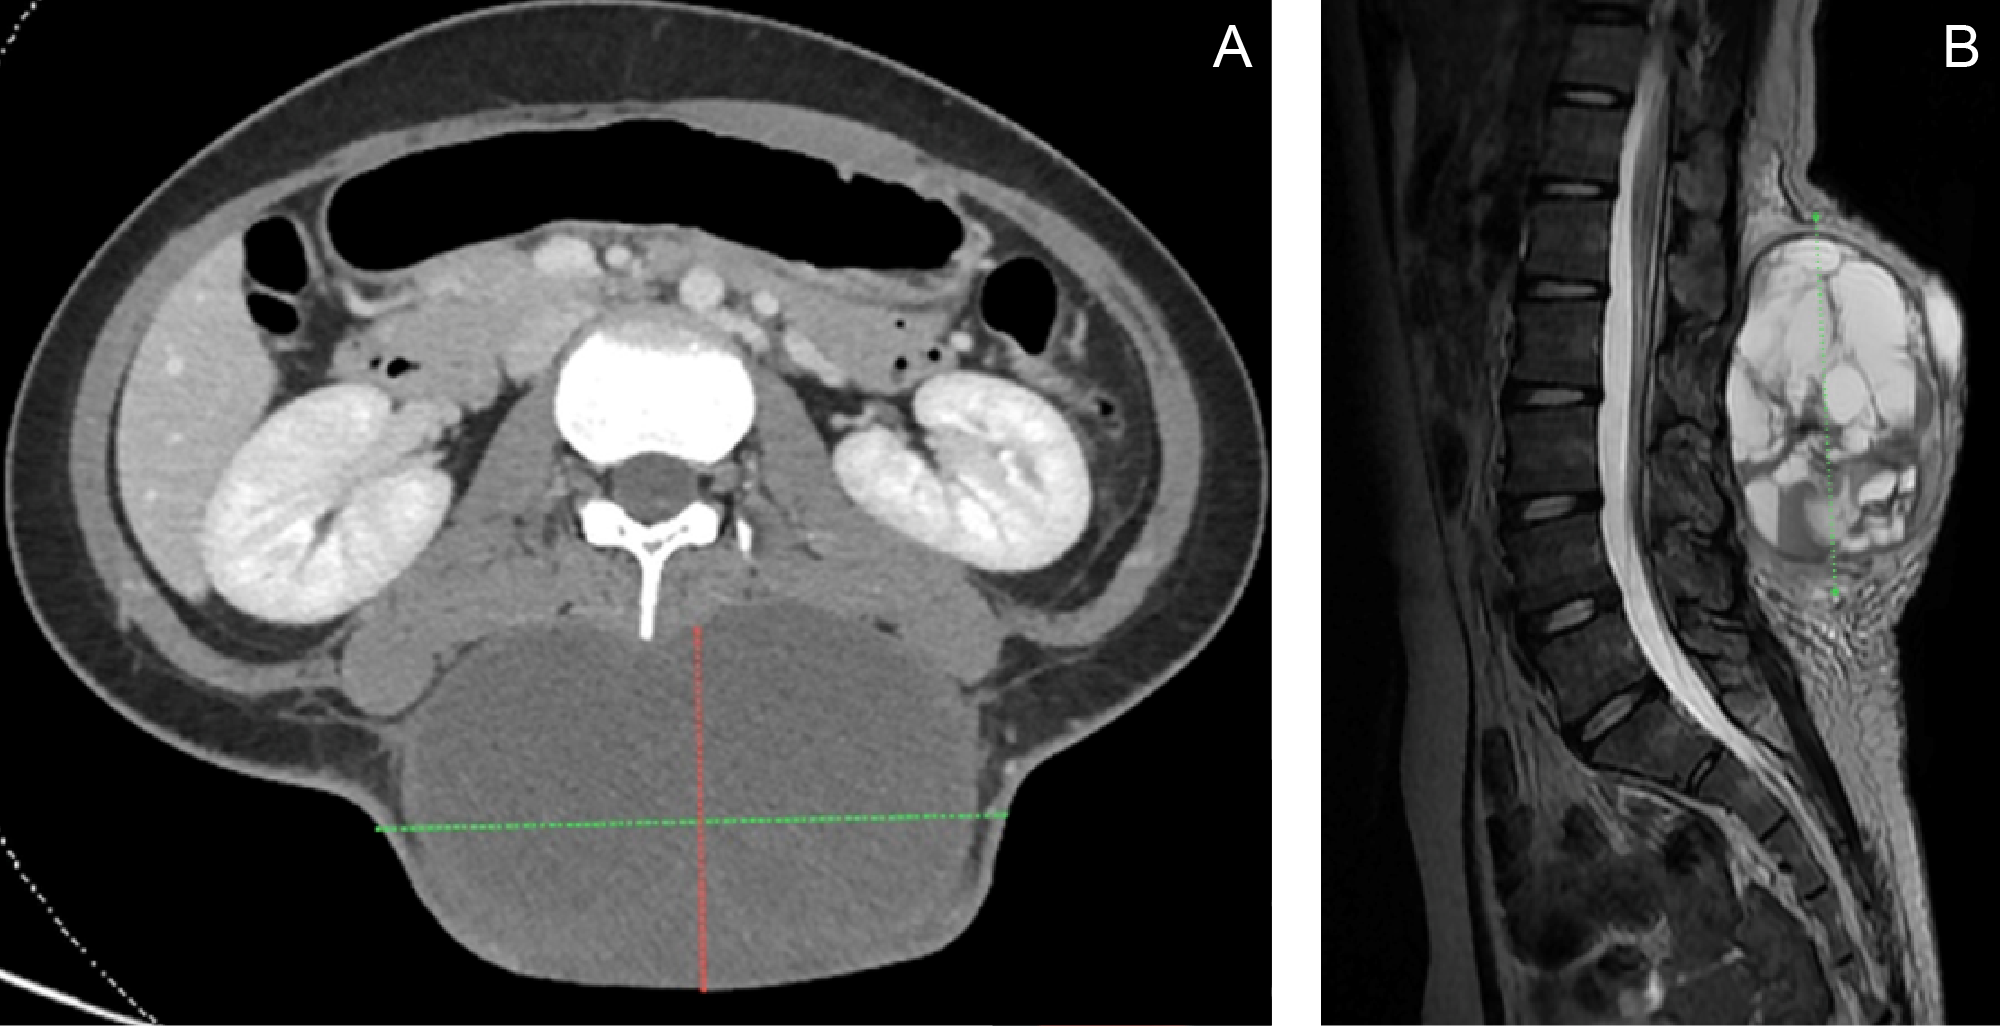

A CT scan and MRI prior to admission revealed an encapsulated, skin-covered, complex cystic soft tissue mass measuring 11.14 × 4.2 × 12.03 cm in the posterior lumbar region, extending from L1 to L5, without evidence of spinal extension (Figure 2). The imaging characteristics demonstrated overlapping features with plexiform neurofibromas, contributing to diagnostic uncertainty.The patient was initially admitted under the Orthopedic Service. On admission, chest and lumbosacral spine imaging confirmed the posterior lumbar mass and additionally revealed intervertebral disc disease at L2–L4, with possible anterolisthesis at L2–L3. She was subsequently referred to Pediatric Oncology and Dermatology for multidisciplinary comanagement. Dermatologic evaluation identified a congenital melanocytic nevus corresponding to the hyperpigmented patch present since birth. The patient was also referred to Plastic and Reconstructive Surgery for planning of soft tissue reconstruction.